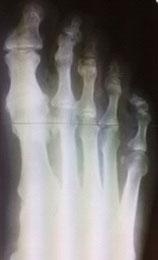

Для диагностики обязательно необходимо провести рентгенографию стопы. Этот метод позволяет выявить костные изменения, разрастания, пограничные дефекты суставных поверхностей, уменьшение суставных щелей, субхондральный склероз костной ткани и наличия кистовидных образований, что дает возможность провести дифференциальную диагностику.

На второй степени проявляется усиленный болевой синдром, которое ограничивает тыльное сгибание (разгибание) I пальца. Рентгенография выявляет субхондральный склероз, уплощение суставных поверхностей и сужение суставного пространства.

На третьей степени боли становятся постоянными и беспокоят даже в состоянии покоя. Тыльное сгибание пальца отсутствует, подошвенное ограничено. Возникает деформация сустава. На рентгенографических изображениях фиксируются костные наросты, выраженная деформация суставных поверхностей.